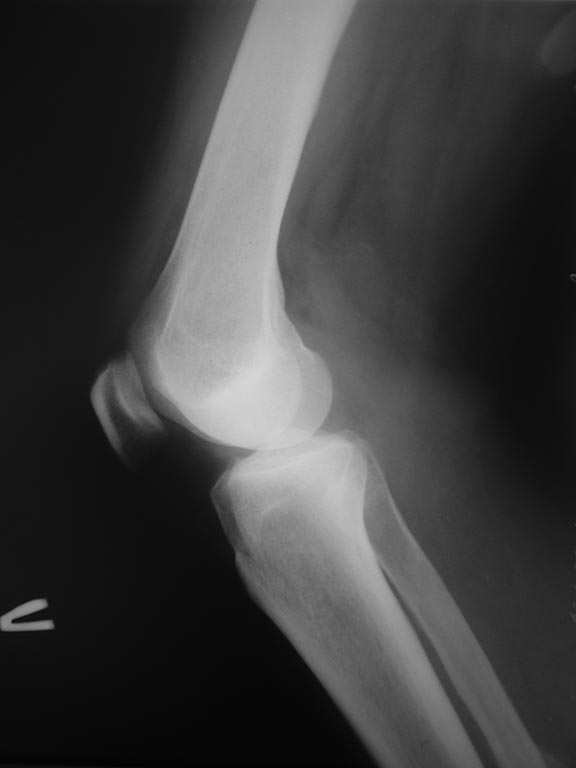

[Ortho] Импрессионный перелом латерального мыщелка левой большеберцевой кости.

Уважаемые коллеги, интересует Ваше мнение по тактике ведения данной

травмы. Мнения коллег разошлись:

1 восстановление высоты с фиксацией блокирующей пластиной и костная

аутопластика

2 консервативное лечение с фиксацией в туторе до 5-6 недель.